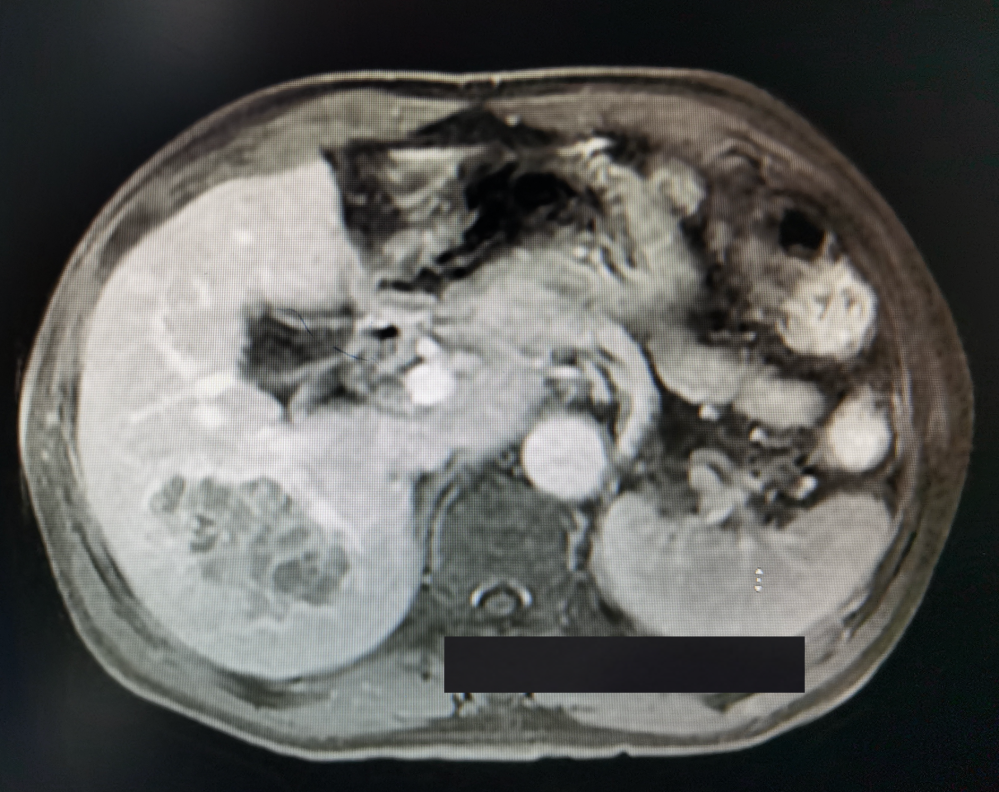

予以酪氨酸激酶抑制剂(TKI) PD-1免疫检查点抑制剂治疗计3个月,其间行两次TACE介入治疗。复查甲胎蛋白下降至26 ng/ml,增强核磁影像提示病灶坏死、缩小、部分子灶消失,较大者位于右后叶右尾状叶,大小12×9 cm,仍见残留多发活性(影像如图2所示)。

图2.转化后核磁影像(滑动浏览)